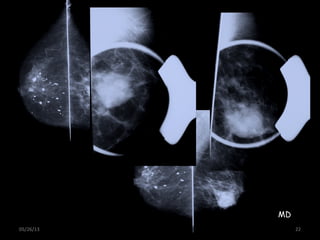

05/26/13 22

MD

05/26/13 21 Inc. Compl:FOCALIZADA • Masas, densidades, desestructuraciones • Usar colimador • Grados de inclinación del tubo, igual a los usados en cada incidencia • Marca en el lado externo de la mama Colimador Paleta compresora MD

• 22.